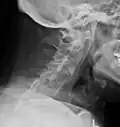

Lateral X-ray of the neck in ankylosing spondylitis -

The earliest changes demonstrable by plain X-ray shows erosions and sclerosis in sacroiliac joints. Progression of the erosions leads to widening of the joint space and bony sclerosis. X-ray spine can reveal squaring of vertebrae with bony spur formation called syndesmophyte. This causes the bamboo spine appearance. A drawback of X-ray diagnosis is the signs and symptoms of AS have usually been established as long as 7–10 years prior to X-ray-evident changes occurring on a plain film X-ray, which means a delay of as long as 10 years before adequate therapies can be introduced.[25]